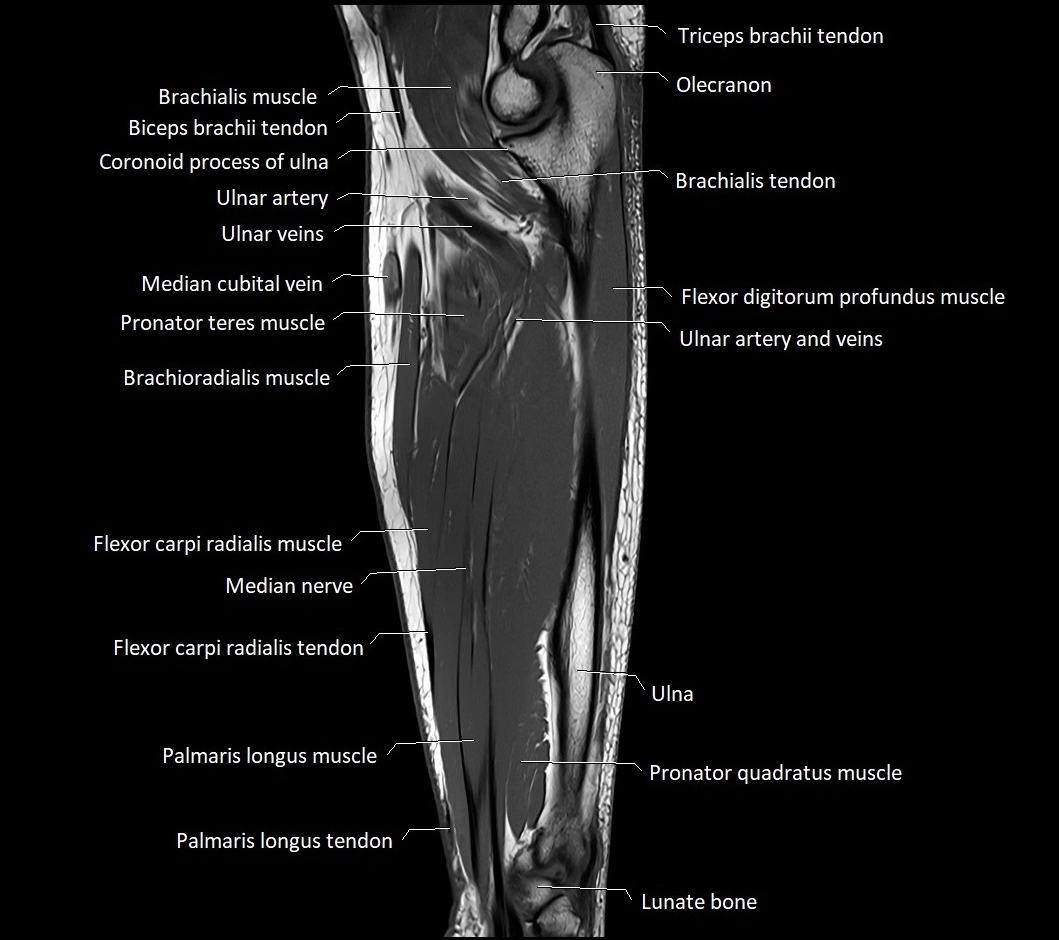

MRI images

image